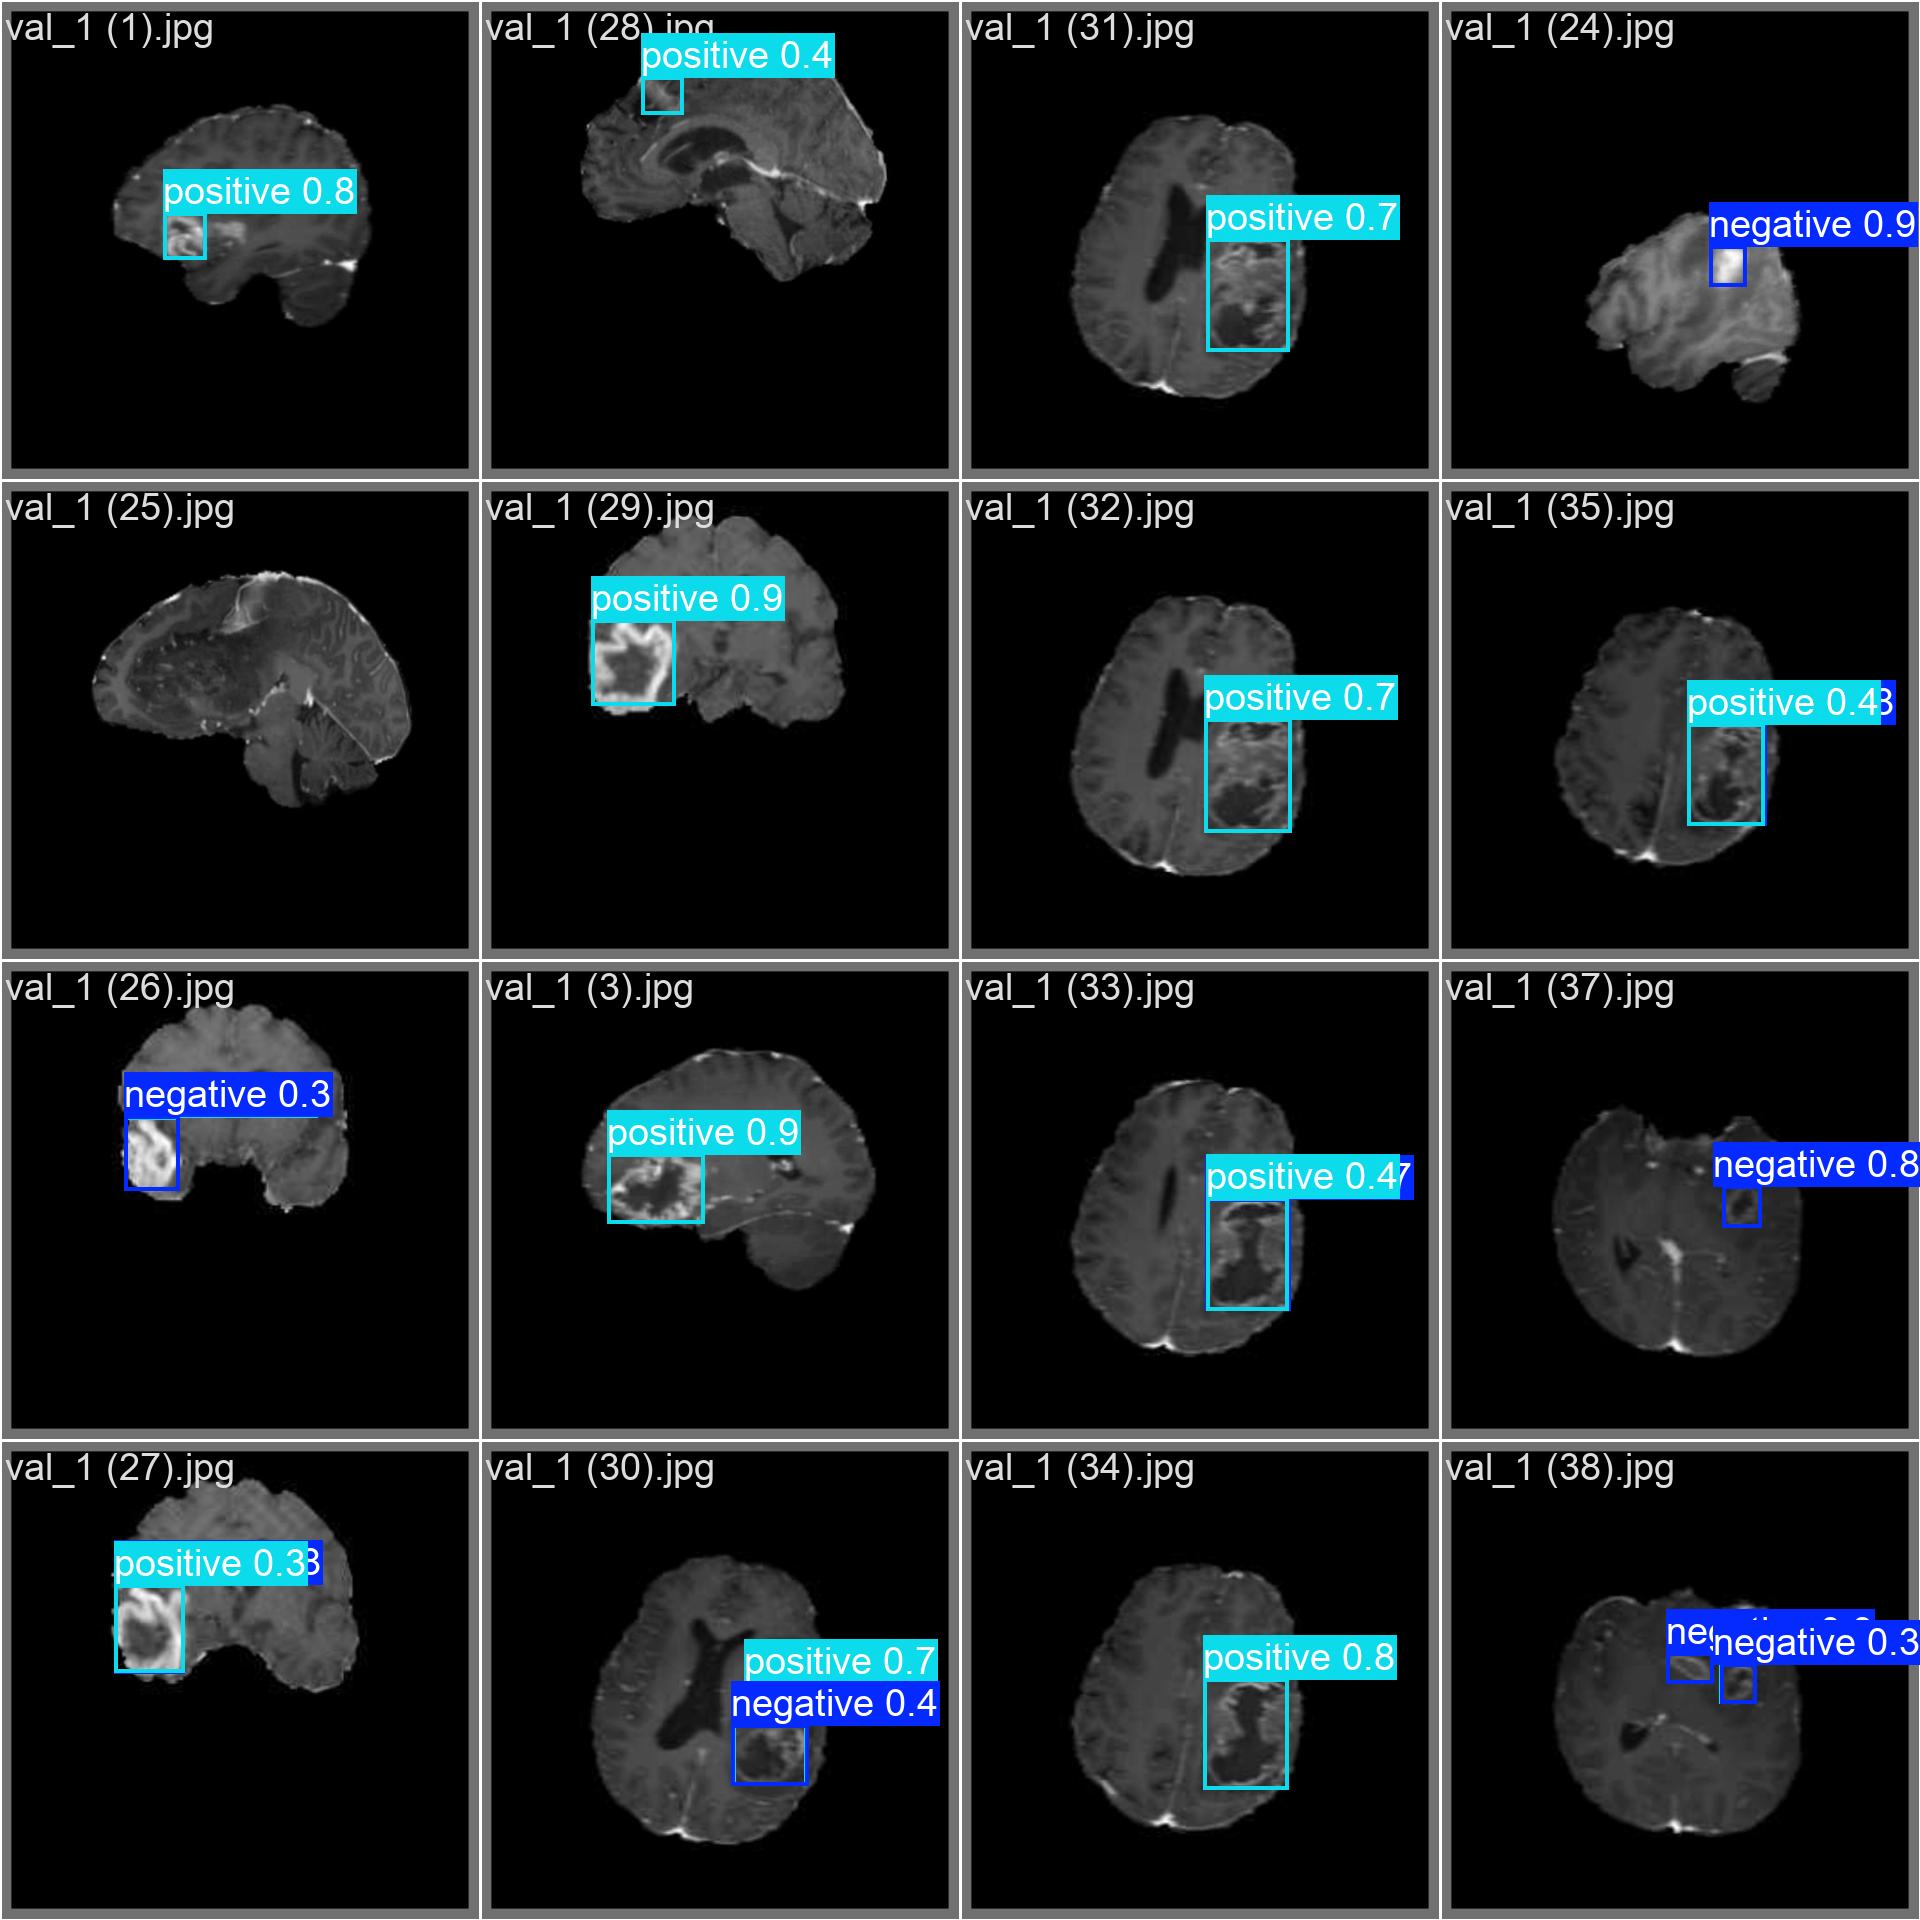

negative:表示图像中存在阴性肿瘤(如良性、低级别或无活性病灶)positive:表示图像中存在阳性肿瘤(如恶性、高级别或活跃增殖病灶)

⚠️ 注:此处"阴性/阳性"指肿瘤的生物学行为或临床意义,具体定义需依据标注规范。

5.2 图像检测

python

# 读取图像

img_path = 'mri_slice.jpg'

img = cv2.imread(img_path)

# 使用模型进行预测

results = model(img)

# 解析结果

for result in results:

boxes = result.boxes # 获取边界框

for box in boxes:

# 提取坐标和置信度

x1, y1, x2, y2 = box.xyxy[0].cpu().numpy().astype(int)

conf = box.conf.cpu().numpy()[0]

cls = int(box.cls.cpu().numpy()[0])

label = model.names[cls] # 'negative' 或 'positive'

# 在图像上绘制边界框和标签

color = (0, 255, 0) if label == 'negative' else (0, 0, 255) # 绿色/红色区分

cv2.rectangle(img, (x1, y1), (x2, y2), color, 2)

cv2.putText(img, f'{label} {conf:.2f}', (x1, y1 - 10),

cv2.FONT_HERSHEY_SIMPLEX, 0.9, color, 2)

6. 结果与分析

- 精度 : 通过测试集评估模型的 mAP@0.5 等指标,YOLOv12 在高质量标注数据上通常能达到较高精度。

- 速度: YOLOv12 推理速度快,能满足单帧 MRI 图像的实时检测需求。

- 鲁棒性: 模型对不同 MRI 模态、噪声、部分遮挡具有一定鲁棒性。